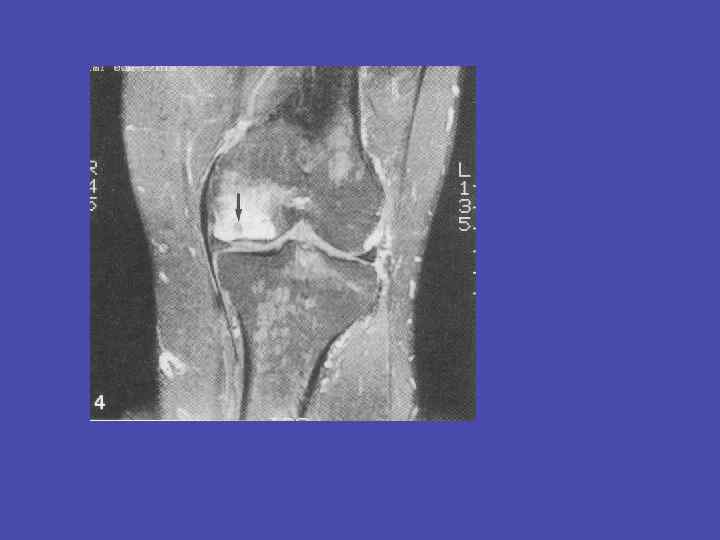

Туберкулезный гонит, предартритическая фаза 56

Туберкулезный гонит, предартритическая фаза 57

Туберкулезный гонит, артритическая фаза 59